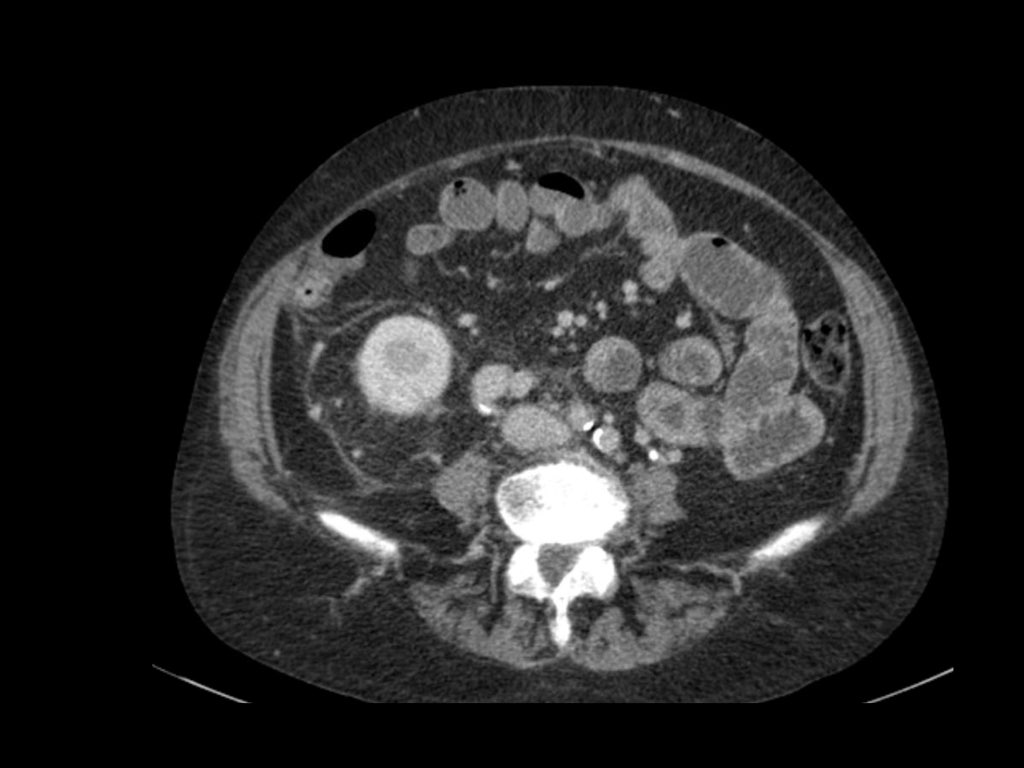

Tổn thương xâm lấn ở cực dưới thận phải, phát triển đáng kể sau sáu tháng, kèm theo hạch bạch huyết lan rộng. Đây được xác định là di căn của ung thư phổi.

Di căn thận thường có kích thước nhỏ, đa ổ và hai bên, với hình thái phát triển xâm lấn.

Các tổn thương này ngấm thuốc nhẹ, kém hơn nhiều so với nhu mô thận bình thường.

Hình ảnh cho thấy bệnh nhân có nhiều tổn thương di căn thận.

Lưu ý huyết khối khối u trong tĩnh mạch thận trái.

Đây là hình ảnh của một bệnh nhân ung thư phổi.

Có một tổn thương di căn ở thận trái và nhiều tổn thương di căn hạch bạch huyết (mũi tên).

Nếu đây là biểu hiện duy nhất, sẽ rất khó để phân biệt với ung thư biểu mô tế bào thận có di căn hạch bạch huyết.